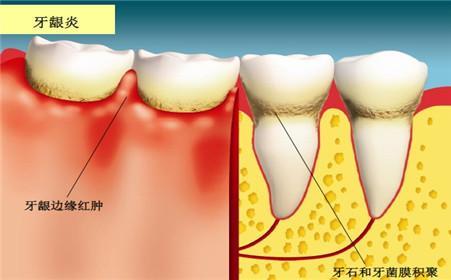

1、导致牙龈出血:牙龈炎

许多人吃辛辣刺激的食物,隔天早上刷牙发现牙龈肿胀,一旦刷牙就牙龈出血,其实就是上火引起的,本来已经是体内火气过盛,导致牙龈发炎,牙龈表皮比较脆弱,这时刷牙会造成二次伤害,刺激到牙龈,出血会更严重。